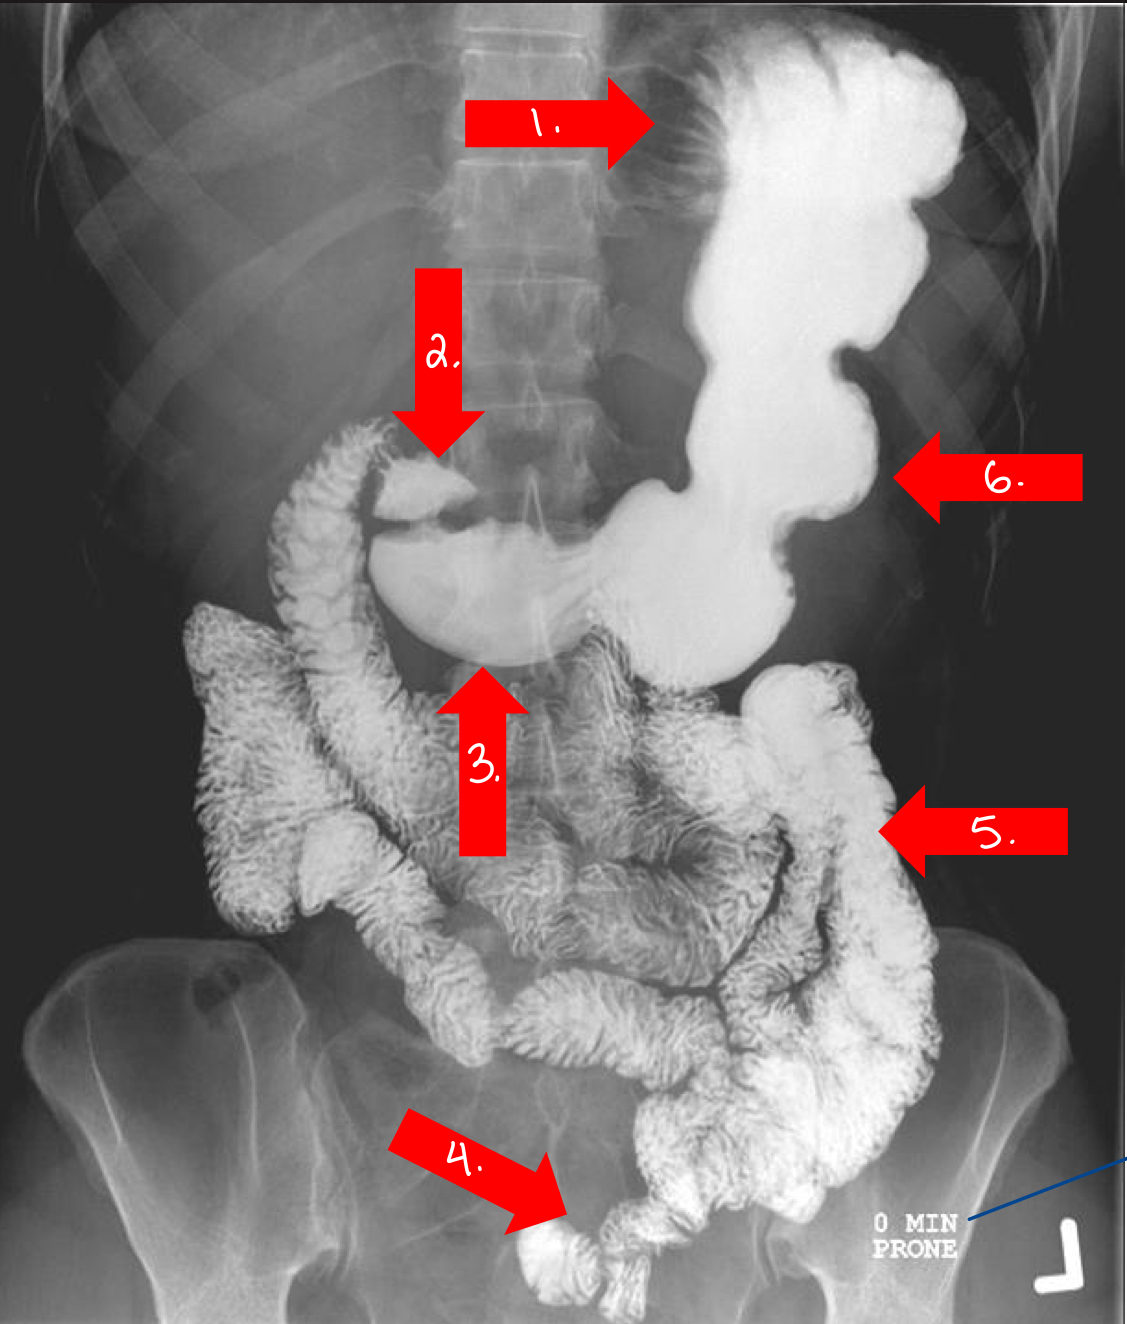

What is 1

fundus/stomach

What is 2

duodenal bulb/small intestine

What is 3

pylorus

or pyloric antrum

What is 4

ileum/small intestine

What is 5

jejunum/small intestine